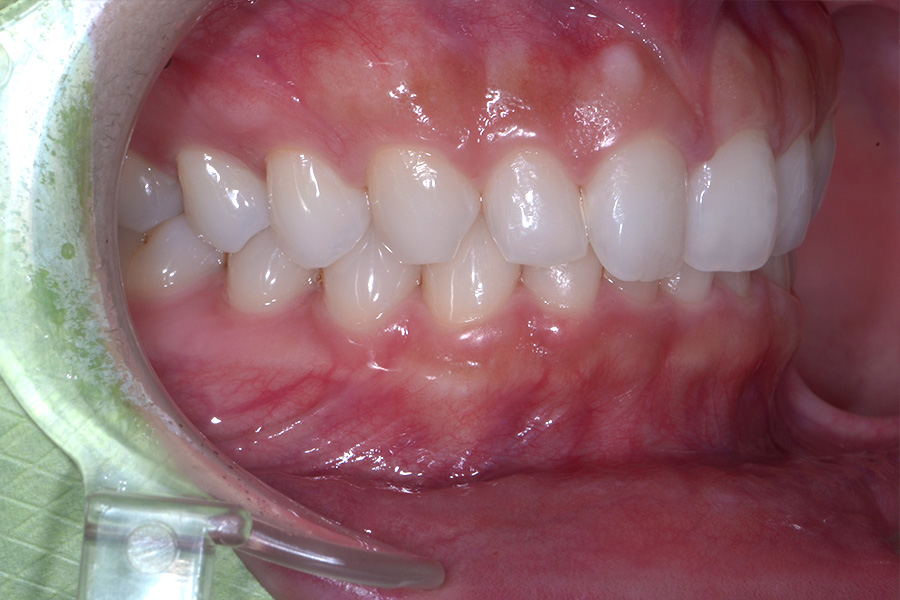

治療前

治療後

主訴 前歯のすきっ歯と捻じれを治したい

治療内容 上下顎ラビアル矯正(表側矯正)